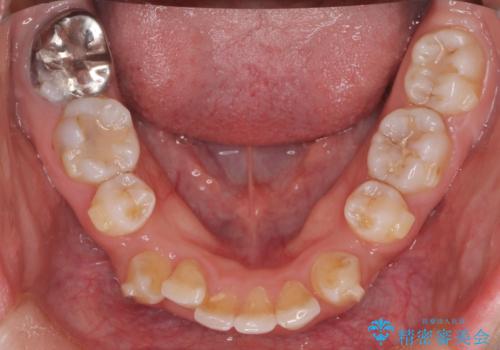

- 前歯から奥歯にかけて歯の重なりが激しい歯のがたつき(重度叢生)を主訴にご来院されました。精密検査の結果、歯が並ぶスペースが大幅に不足しており、歯並びを整え、口元を美しく引っ込めるためには、スペースの確保が必要と診断しました。そこで、上下左右の第一小臼歯(4番目の歯)を計4本抜歯し、そのスペースを利用して歯並び全体を整える抜歯矯正の治療計画を立案。装置には、透明で目立たないインビザラインを採用し、審美性と治療効果の両立を目指しました。

今回の治療では、重度の叢生を改善するため、まず計画通り上下左右4本の小臼歯を抜歯し、歯を並べるための十分なスペースを確保しました。装置には透明で取り外し可能なインビザラインを使用。抜歯によってできたスペースを最大限に活用し、マウスピースを定期的に交換しながら、デコボコを解消しつつ、前歯を効果的に後退させました。

治療の結果、長年の悩みであった重度の歯のがたつきが解消され、口元の突出感も改善。機能的にも安定し、審美的にも美しい、理想的な歯並びを獲得していただけました。